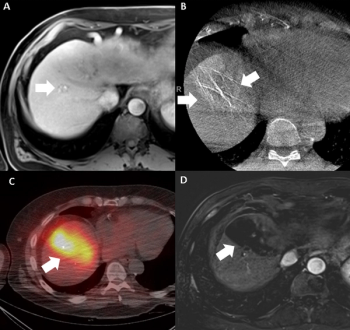

Reviewing recent changes to the Barcelona Clinic Liver Cancer (BCLC) staging system for hepatocellular carcinoma and the potential impact for interventional radiologists, these authors discuss key updates including the subdivision of patients with intermediate stage disease and emerging literature on systemic agents for advanced disease.